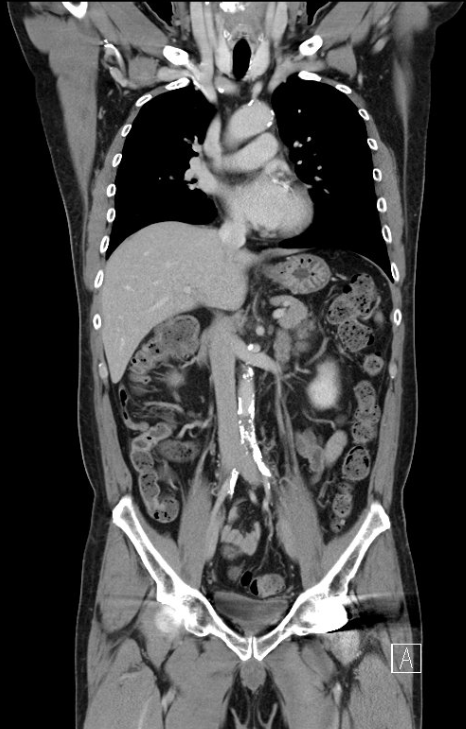

Relevant Test Results Prior to Catheterization

ABI measured on December 13, 2021, was 0.64on the right and 0.59 on the left. Duplex ultrasonography performed on August6, 2024, revealed monophasic flow in bilateral CFA, SFA, popliteal, ATA, andPTA arteries, favoring bilateral severe iliac artery disease. Subsequent CTangiography on November 15, 2024, demonstrated aortoiliac occlusive disease,without evidence of aneurysm or distal vessel obstruction. Laboratory databefore admission showed HbA1c 6.9% and LDL 76 mg/dL.

Diagnosticangiography revealed total occlusion of both common iliac arteries, while theexternal iliac arteries remained patent bilaterally. The lesions wereconsistent with aortoiliac occlusive disease (Leriche syndrome), and the distalflow was preserved via collateral circulation.